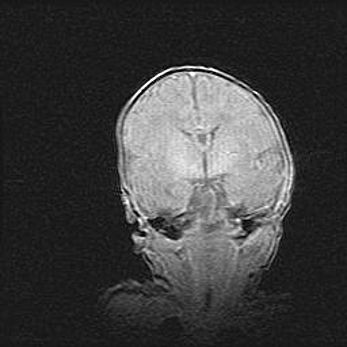

Наружная гидроцефалия с возможной атрофией височных областей.

Возраст: 28 дней

Вес: 3670 г

Пол: мужской

Окружность головы: 38 см

Срок гестации: 40 недель

Гидроцефалия головного мозга у новорожденных – это заболевание, которое характеризуется скоплением избыточного количества спинномозговой жидкости в желудочковой системе головного мозга в результате затруднения её перемещения от места выработки к месту поглощения в кровеносную систему или вследствие нарушения абсорбции. При открытой наружной форме гидроцефалии у новорожденных расширяются и переполняются субарахноидные пространства.

При нормотензивных  формах,  которые,  как  правило,  являются  следствием  перенесенных ишемических  повреждений  паренхимы  мозга,  возможно  сочетание микроцефалии  с нормотензивной гидроцефалией. В основе данных изменений лежит атрофия больших полушарий с преимущественной  локализацией  в  лобно-височных  областях.